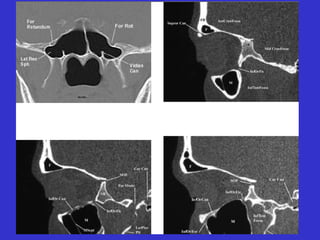

Este documento describe las diferentes proyecciones radiográficas utilizadas para examinar los senos paranasales, incluyendo las proyecciones básicas de Caldwell, Waters lateral y las proyecciones especiales como Hirtz y Waters mentonasal. También describe las diferentes estructuras anatómicas que componen el complejo ostiomeatal anterior y posterior de los senos paranasales.